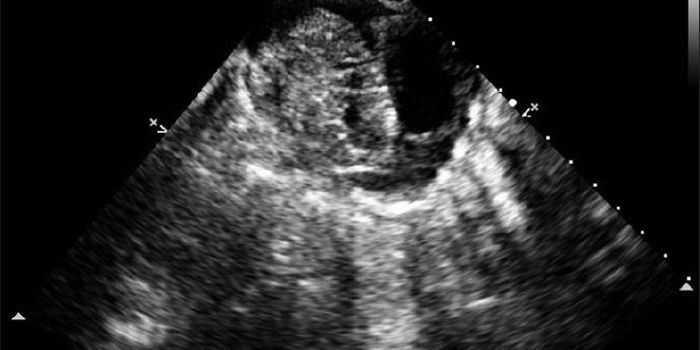

Cardiology is an ever-evolving branch of medicine concerned with disease and disorders of the heart. Cardiology trending provides articles and resources to keep you informed on risk factors, causes and prevention of heart disease, evidence-based research and advances in treatment.